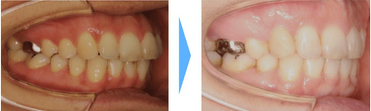

【口ゴボ】

口ゴボは上下の顎と歯が前に突き出ている状態です。前に突き出た上唇は口角に向かって下がっているように見えます。下唇は口を閉じようとして力が入るため口角を引き下げます。

歯を動かすスペースを作るために抜歯を行った症例です。

口元を大きく変化させるためにはやはり、唇を裏側から支える上下の前歯の位置を大きく変化させる必要があります。

小臼歯4本の抜歯が必要になりましたが、治療後口元をスッキリと後ろに下げることができました。

症例情報

【患者】 30代女性

【主訴】 前歯の突出

【治療期間】2年3ヶ月 通院回数20回

【治療内容】上下左右の小臼歯4本を抜歯した後、マウスピース型カスタムメイド矯正歯科装置(製品名インビザライン 完成物薬機法対象外)を使用して主訴である前歯の突出の改善を行いました。

【費用】88万(税込)

【リスク】矯正歯科装置を付けた後しばらくは違和感、不快感、痛みなどが生じることがあります。

矯正中は矯正歯科装置が歯の表面についているため食物が溜まりやすく、また歯が磨きにくくなるため、虫歯や歯周病が生じるリスクがあります。

歯を動かすことにより歯根が吸収して短くなることや歯肉がやせて下がることがあります。

矯正歯科治療は公的健康保健の適応外の自費治療(自由診療)となります。